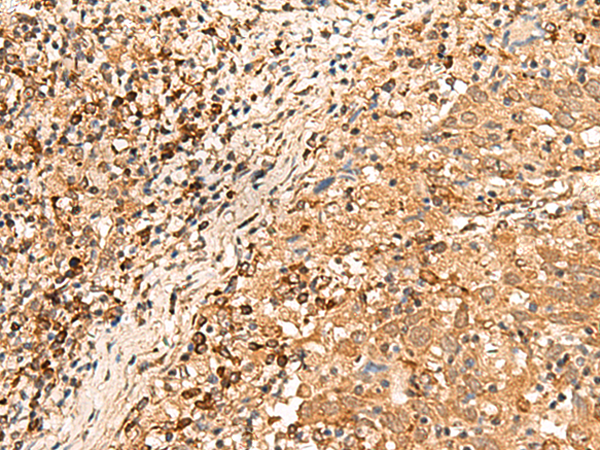

IHC positive control: |

Human cervical cancer |

IHC Recommend dilution: |

30-150 |